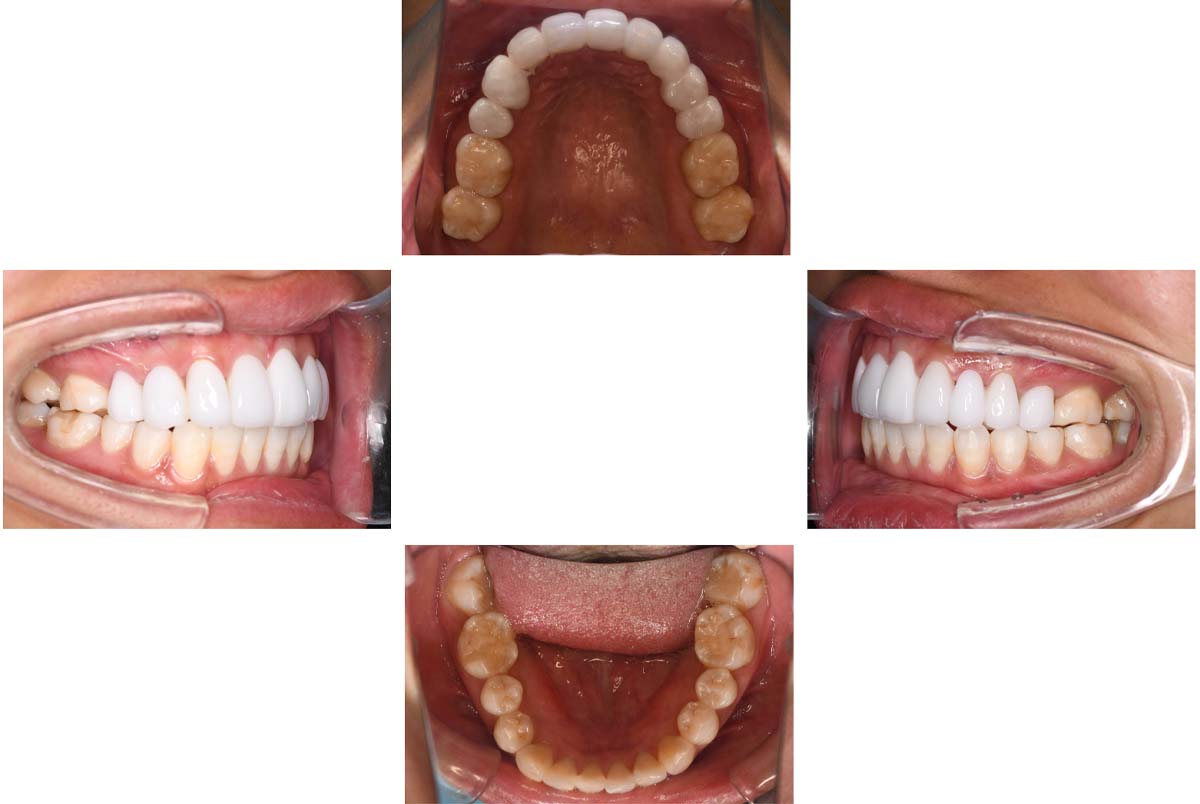

バイトアップ後

![]() |